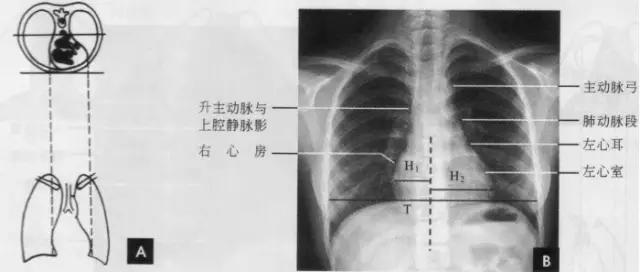

(一)后前位 正常心影2/3位于中线左侧,1/3位于右侧,心尖指向左下,心底部朝向右后上方,形成斜的纵轴。后前位心脏大血管有左右两缘:心右缘分为两段,上段为升主动脉与上腔静脉的总合影,在幼年和青年人边缘主要为上腔静脉影向上延伸,在老年人常见纡曲延长的升主动脉影突出于上腔静脉边缘之外;心右缘下段为右心房所构成,有时在心瞩角内可见一向外下方倾斜的三角形影,为下腔静脉攻肝静脉影,深吸气时明显。心左缘分为三段,上段为主动脉弓;中段为肺动脉主干,但偶尔可为左稀动脉构成,称肺动脉段或心腰,此段较低平或稍突出:下段由左心室构成,左心室在下方形成心尖。左心室与肺动脉之间有长约10cm的一小段,由左心耳构成,正常时不能与左心室区分。透视下左心室与肺动脉段的搏动方向相反,两者的交点称相反搏动点,该点上下两侧心缘里“翘翘板”样运动,该点位置是衡量左右心室增大的一个重要标志。肥胖人左心膈角常有脂肪垫充填,为密度较低的软组织影。后前位能了解心胸及肺循环概况,正常人心(h1+h2)胸(t)比率不大于0.5(如下图)。